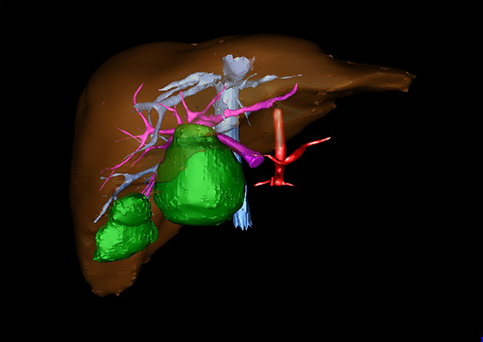

图11:先天性胆管扩张症梭状型三维重建虚拟肝脏、胆道显像

a 图为术前二维CT扫描图像,箭头指示肝内胆管扩张;b 图为CT经多平面重组技术(MPR)所得的重建图像,可粗略地判断病变胆管的位置;c 图示术前Hisense CAS三维重建清晰显示胆管的病理形态及其与肝内三套血管系统的解剖关系;d 图示胆道系统与其伴行的门静脉系统的空间解剖关系;e 图为胆道系统立体形态,箭头处指示迷走胆管,源自肝脏直接汇入胆总管。术前规划先将迷走胆管与肝总管吻合成形,再行肝总管空肠Roux-en-Y吻合术。